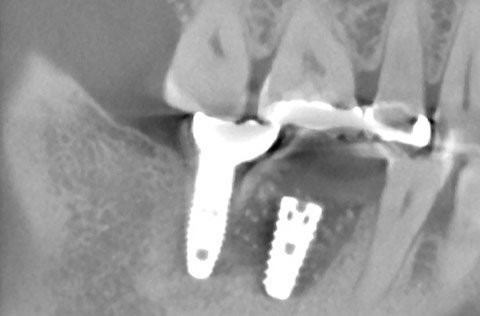

他院でインプラント治療を断られたケース。当院の「ラテラルスリット法」で骨造成を行い、インプラントを埋入できた。